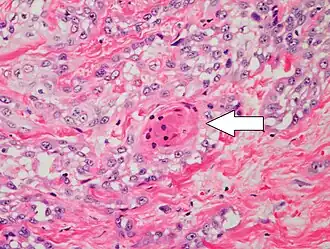

Two types of multinucleated cells may be seen: the first will present as a multinucleated giant cell, and the second will appear as a dyskeratotic cell engulfed in the cytoplasm of a keratinocyte. Occasionally, cells of the upper epidermis will undergo vacuolization, demonstrating an abundant and strongly eosinophilic cytoplasm. There may be a mild to moderate lymphohistiocytic infiltrate detected in the upper dermis.[12]

-

Histopathology of squamous-cell carcinoma in situ (black arrow), compared to normal skin, showing marked atypia. -

Squamous-cell carcinoma in situ, showing prominent dyskeratosis and aberrant mitoses at all levels of the epidermis, along with marked parakeratosis.[12]